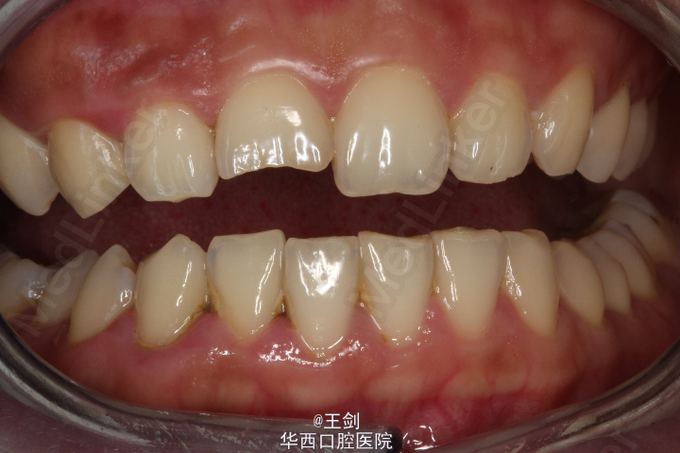

拟行CAD/CAM贴面修复11牙,当天备牙,当天戴牙

CAD/CAM 技术制作贴面可以达到高度密合,大大节省诊疗时间等优点